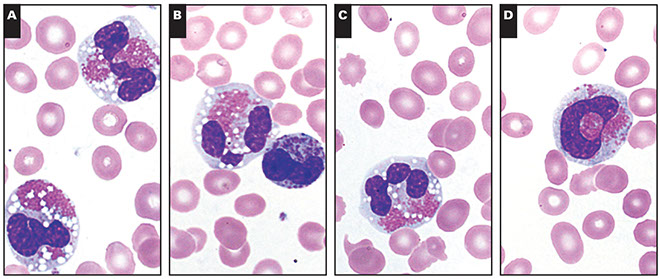

Approach to PB and BM Eosinophilia

• Eosinophil cytology

– Normal: 2-3 lobes, red-orange large granules pack the cytoplasm

– Abnormal: Alterations in segmentation and granulation, vacuolization

– Abnormal cytologic features are seen more often in primary clonal states but are not exclusive

– Eosinophil cytology (abnormal) should not be used alone to indicate clonal eosinophilic disease

Abnormal eosinophil morphology in peripheral blood from a 49-year-old man (case 142) with PDGFRA rearrangement.Eosinophils show abnormal nuclear hypersegmentation, ring form, uneven granulation, or hypogranulation [6]